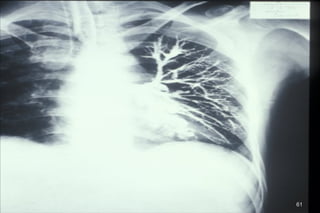

BRONCHIECTASIS

A destructive lung disease characterized by:

● Abnormal & permanent dilatation of medium sized

bronchi

● An associated, persistent and variable inflammatory

process producing damage to bronchial elastic and

muscular elements

59